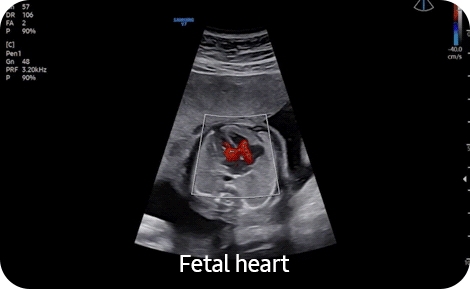

• XI-STIC- Модуль объёмной динамической визуализации сердца плода XI STIC. Необходим модуль 4D;

• 5D Heart Color- Модуль автоматического получения 9 стандартных плоскостей сердца плода из объемных данных STIC в соответствии с международными методическими рекомендациями с динамическим отображением кровотока 5D Heart Color. Необходим модуль 4D. (CV1-8AD, EV2-10A);

• MPI +- Модуль автоматического измерения миокардиального индекса MPI (индекса Tei) для оценки функции сердца плода (все внутриполостные датчики, CV1-8AD);

• Cardiac Measure- Пакет кардиорасчетов Cardiac;

• Strain+- Модуль количественной оценки глобальной и локальной сократимости ЛЖ Strain+. (все фазированные датчики). Необходим модуль ЭКГ;

• StressEcho- Модуль Стресс Эхо. (все фазированные датчики). Необходим модуль ЭКГ;

• Auto EF- Модуль автоматического расчета фракции выброса ЛЖ, частоты сердечного ритма, ударного объема ЛЖ, конечного диастолического и конечного систолического объемов ЛЖ. Необходим модуль ЭКГ;